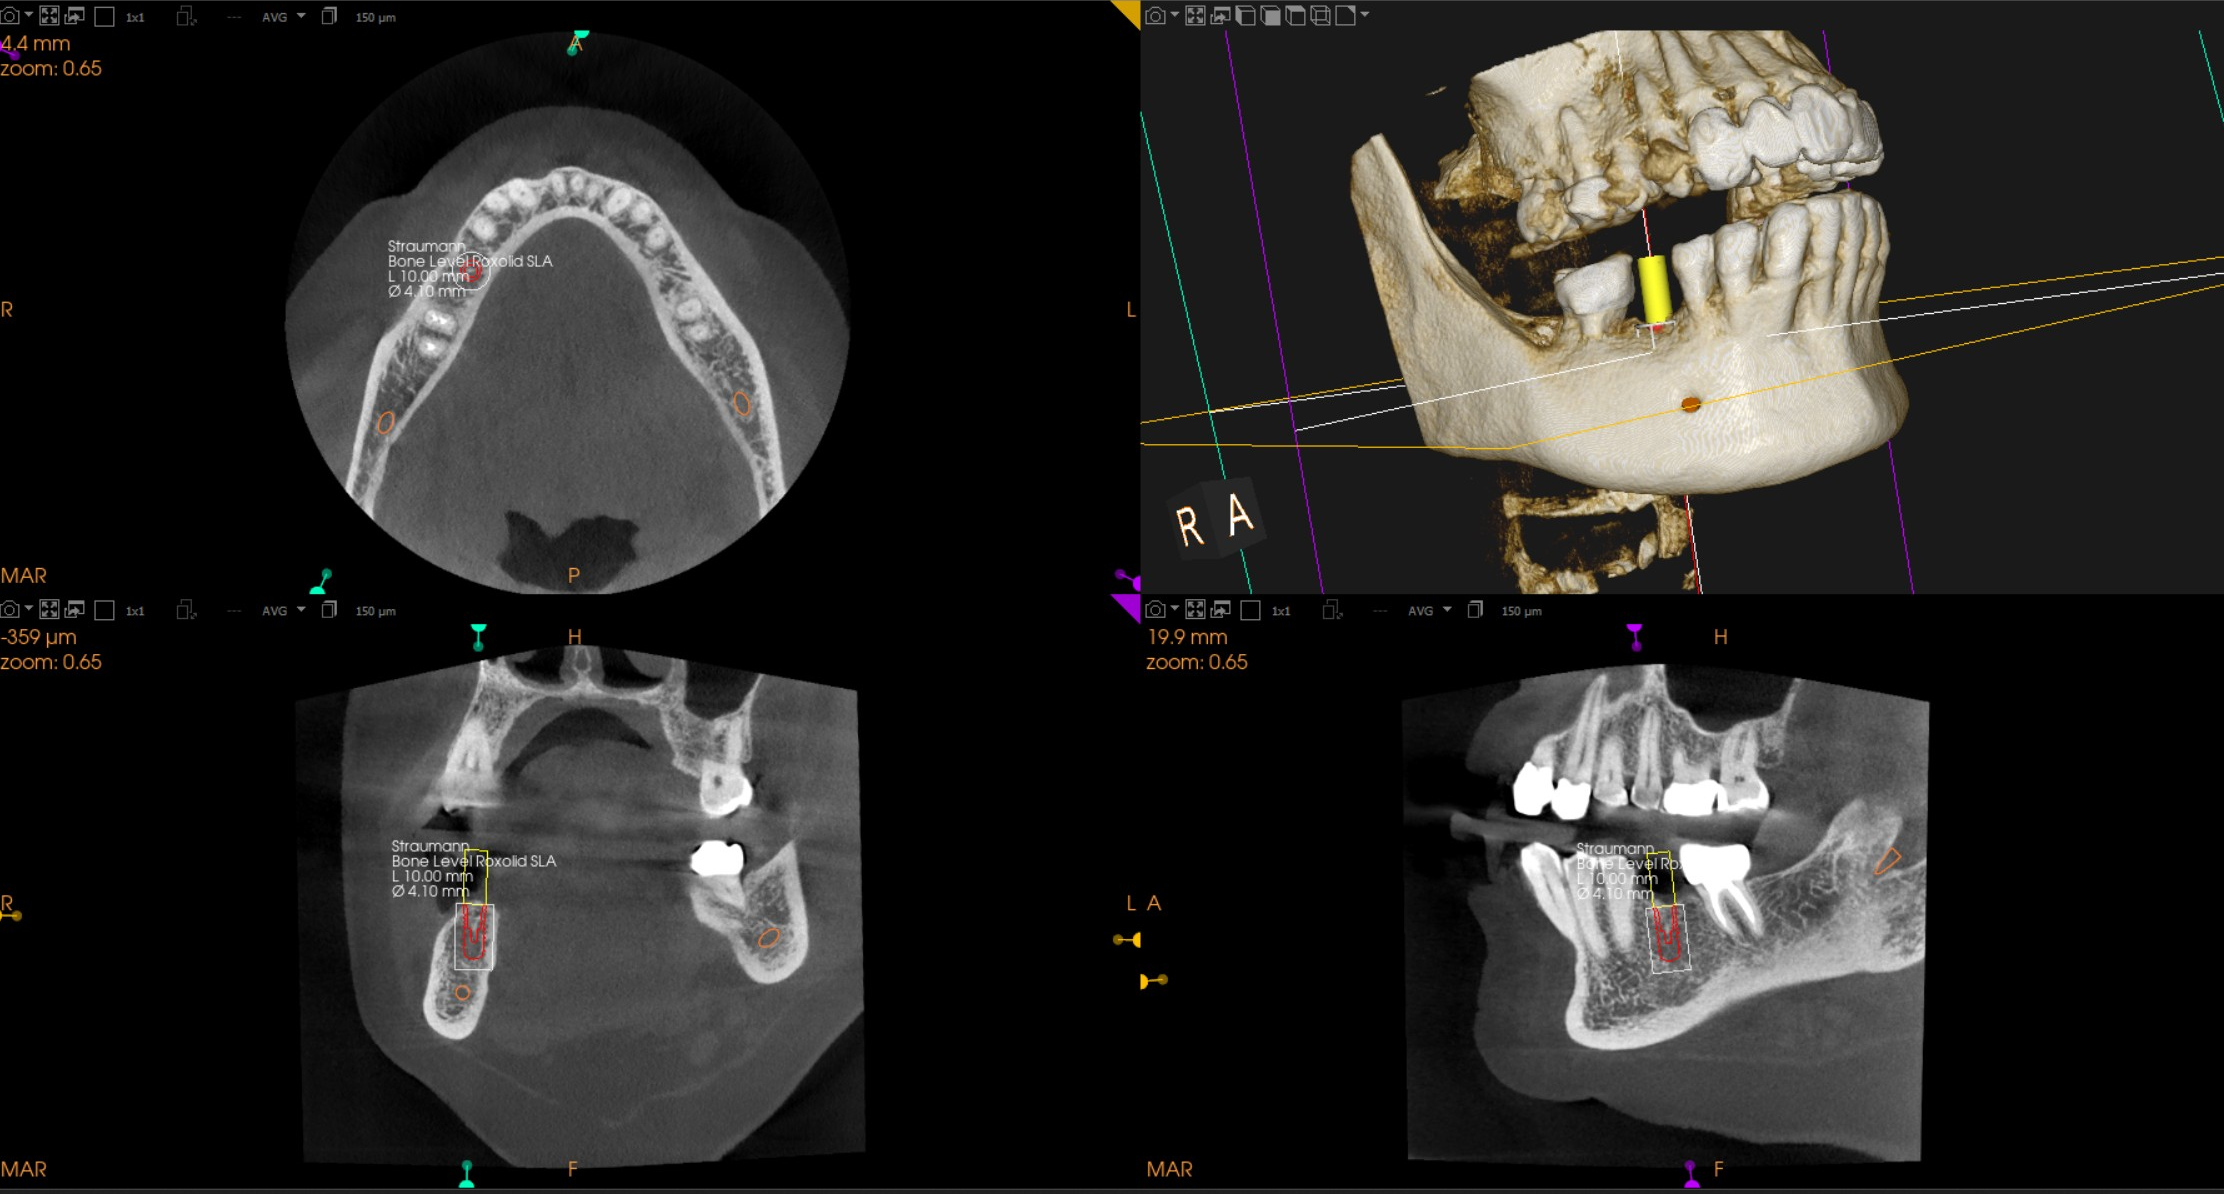

The process starts with a Cone Beam CT scan that captures the important anatomy of the site that needs a tooth replacement. Next, a light weight titanium implant is secured to the maxilla or mandible and a few months after this initial surgery, a prosthetic ceramic tooth can be fixed to the implant.

Precise dental implant planning with our 3D Cone Beam